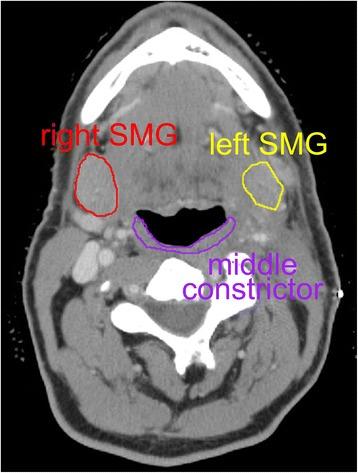

Patients treated with definitive radiation therapy for oropharynx cancer were included in this retrospective study. Those with disease recurrence were excluded. Salivary glands and swallowing-related organs at risk, including pharyngeal constrictors, were contoured. Primary endpoint was time from end of radiation treatment to freedom from gastrostomy (PEG) tube dependence. Cox proportional hazards regression and logistic regression were used to assess influence of normal tissue doses on swallowing related endpoints.

方法

本回顾性研究纳入了接受口咽癌根治性放疗的患者。排除疾病复发的患者。勾勒出唾液腺和吞咽相关的危及器官,包括咽缩肌。主要终点是从放疗结束到无需胃造口(PEG)管依赖的时间。使用Cox比例风险回归和逻辑回归来评估正常组织剂量对吞咽相关终点的影响。